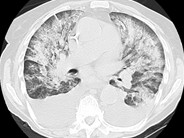

Clinical diagnostic value of spiral CT in invasive pulmonary fungal Chest X Ray Fungal Pneumonia It is important to consider a diagnosis of bacterial pneumonia in a patient with fever and cough when the silhouette. Acute invasive fungal infection was defined as patients with rapid progression of disease clinically or radiographically, and at least one of the followings: When a patient presents with a clinical syndrome of pneumonia, a constellation of factors must be considered. Chest X Ray Fungal Pneumonia.